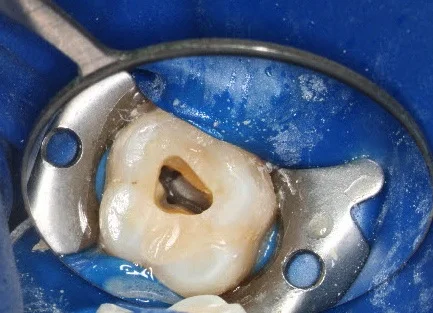

Microscopie: Tot in de kleinste vezels (Nieuw sinds 2026)

Sinds dit jaar tillen we onze wortelkanaalbehandelingen naar een hoger niveau met de introductie van de behandelmicroscoop.

Door te werken met extreme vergrotingen kunnen we verborgen kanalen opsporen die met het blote oog onzichtbaar blijven.

Hogere slaagkans: We zien precies of de kanalen schoon en droog zijn, wat de duurzaamheid van de behandeling enorm vergroot.

Zorgvuldigheid: De behandeling duurt misschien iets langer, maar het resultaat is een tand die veel langer behouden kan blijven.